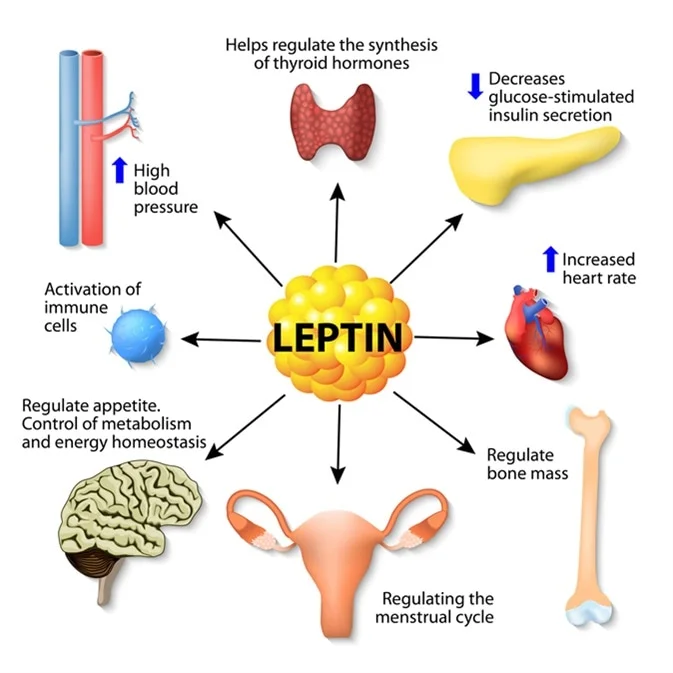

Leptin: The Pain Amplifier

Leptin is a 16-kDa protein your fat cells make. More body fat means more leptin. This molecule stimulates IL-6, IL-8, and TNF-α in your joint tissues. These are inflammatory signals that cause pain and swelling.

Leptin hits cartilage cells directly. It triggers pathways that break down the cushioning matrix. Women typically have higher leptin levels than men. This partly explains why women get OA more often. The more you weigh, the more leptin you make. And the more your joints suffer.